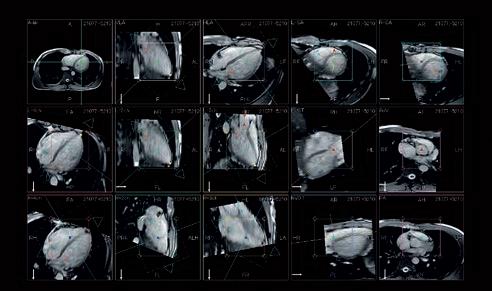

Cardiac screening for proactive health surveillance is firmly on the radar for all sporting organisations. This is not only to identify undetected anomalies that could put life and health at risk, but also to monitor for the onset of coronary artery disease as players age. Indeed, from youth teams to the veteran professional footballer, anyone undertaking vigorous training and competitive matches is regulated to receive cardiology profiling every 2 years1

The imaging tool that has traditionally been used is ultrasound echocardiography, looking at the structure of the heart at rest and during stress exercise. Now, and increasingly, the structure and functionality of the heart is examined via the latest generation in MRI.

For example, new developments have accelerated the examination time for cardiac MRI, with fewer patient breath holds needed to deliver much more detailed, richer image outputs that give another level of screening and profiling of the more subtle presentations of cardiac anatomy.